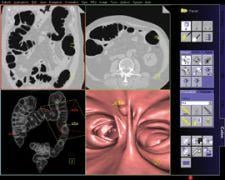

The syngo Colonography PEV (Polyp Enhanced Viewing) by Siemens Medical Solutions is an automated second reader tool for the visualization of lesions in the colon. The solution helps radiologists to detect polyp-shaped objects between 6 millimeters and 25 millimeters in size and can now be used both in clean-prepped and solid-liquid tagged protocols.